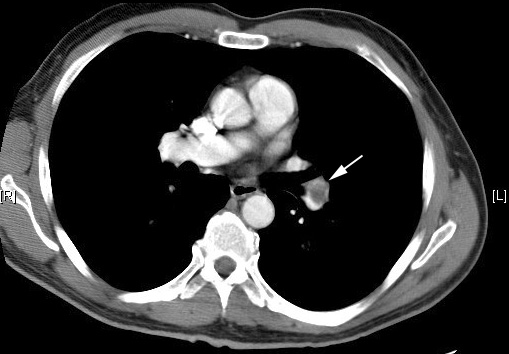

1-CT : To see across your lung

[Image: jay99b.jpg]